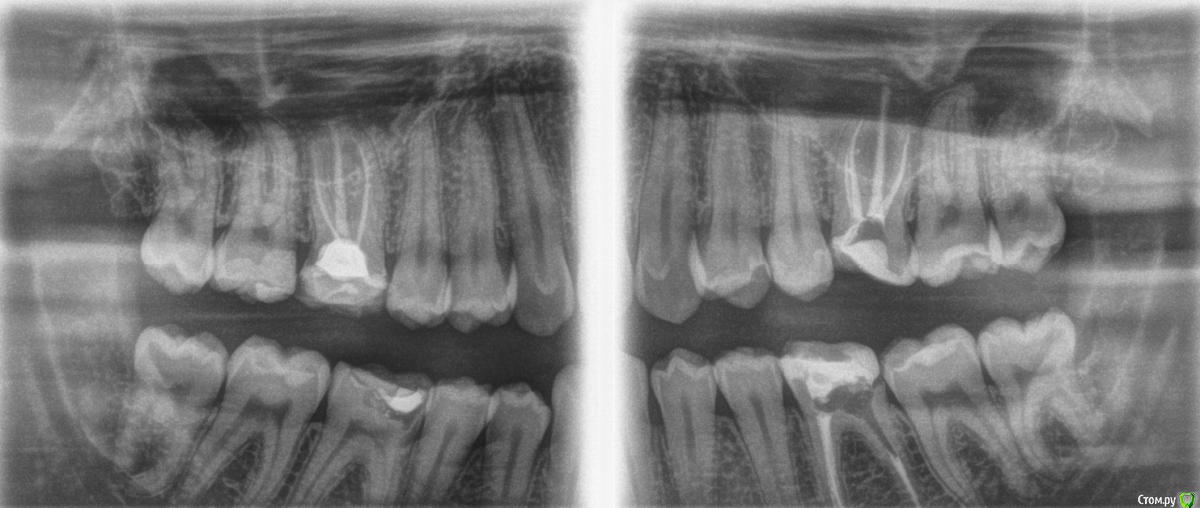

son-leta Опубликовано 19 апреля, 2017 Поделиться Опубликовано 19 апреля, 2017 Добрый вечер! Прошу рекомендаций по поводу лечения всех четырёх 6-к (если ещё что-то, то тоже). Зубы 1.6, 2.6 и 3.6 подготавливаются под покрытие коронками, нужно ли что-то перелечивать? И что делать с 4.6? Мы живём в Германии, врачи говорят разное. Ссылка на комментарий

Pan Опубликовано 22 апреля, 2017 Поделиться Опубликовано 22 апреля, 2017 По моему скромному мнению перелечивания не требуется, если с момента первичного лечения прошло не менее 2-х лет . Ссылка на комментарий

son-leta Опубликовано 22 апреля, 2017 Автор Поделиться Опубликовано 22 апреля, 2017 По моему скромному мнению перелечивания не требуется, если с момента первичного лечения прошло не менее 2-х лет .Спасибо за ответ. 3.6 лечили 1,5 года назад, остальные зубы раньше Ссылка на комментарий